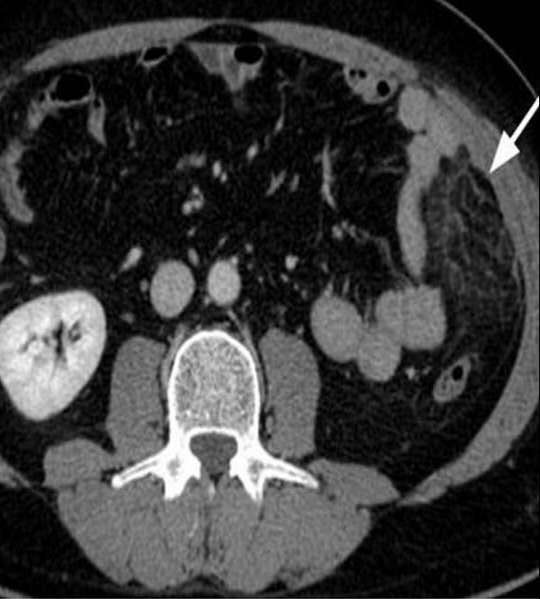

3:肠脂垂炎和网膜梗塞:

肠脂垂炎和网膜梗塞:肠脂垂是沿结肠袋两侧分布的许多小脂肪突起,乙状结肠较多。肠脂垂扭转可造成局部缺血引起炎症。正常的肠脂垂CT上无法看到。肠脂垂炎典型CT表现是;结肠旁脂肪密度结节,边缘局限增高(腹膜炎症增厚可能),伴有中心高密度灶(血栓可能)。

网膜梗塞可能的原因有肥胖、创伤、近期手术史或剧烈活动等。CT表现:网膜不均匀密度脂肪肿块。与肠脂垂炎相比,两者CT表现类似,前者病灶范围大(大于5cm),无中心密度增高灶。两者不易区分时可统称为“腹腔局灶性脂肪坏死”。肠脂垂炎多发生在左下腹,网膜梗塞多见右上及下腹。

肠脂垂炎和网膜坏死是自限性疾病,保守治疗即可。CT检查可明确诊断,避免过度治疗